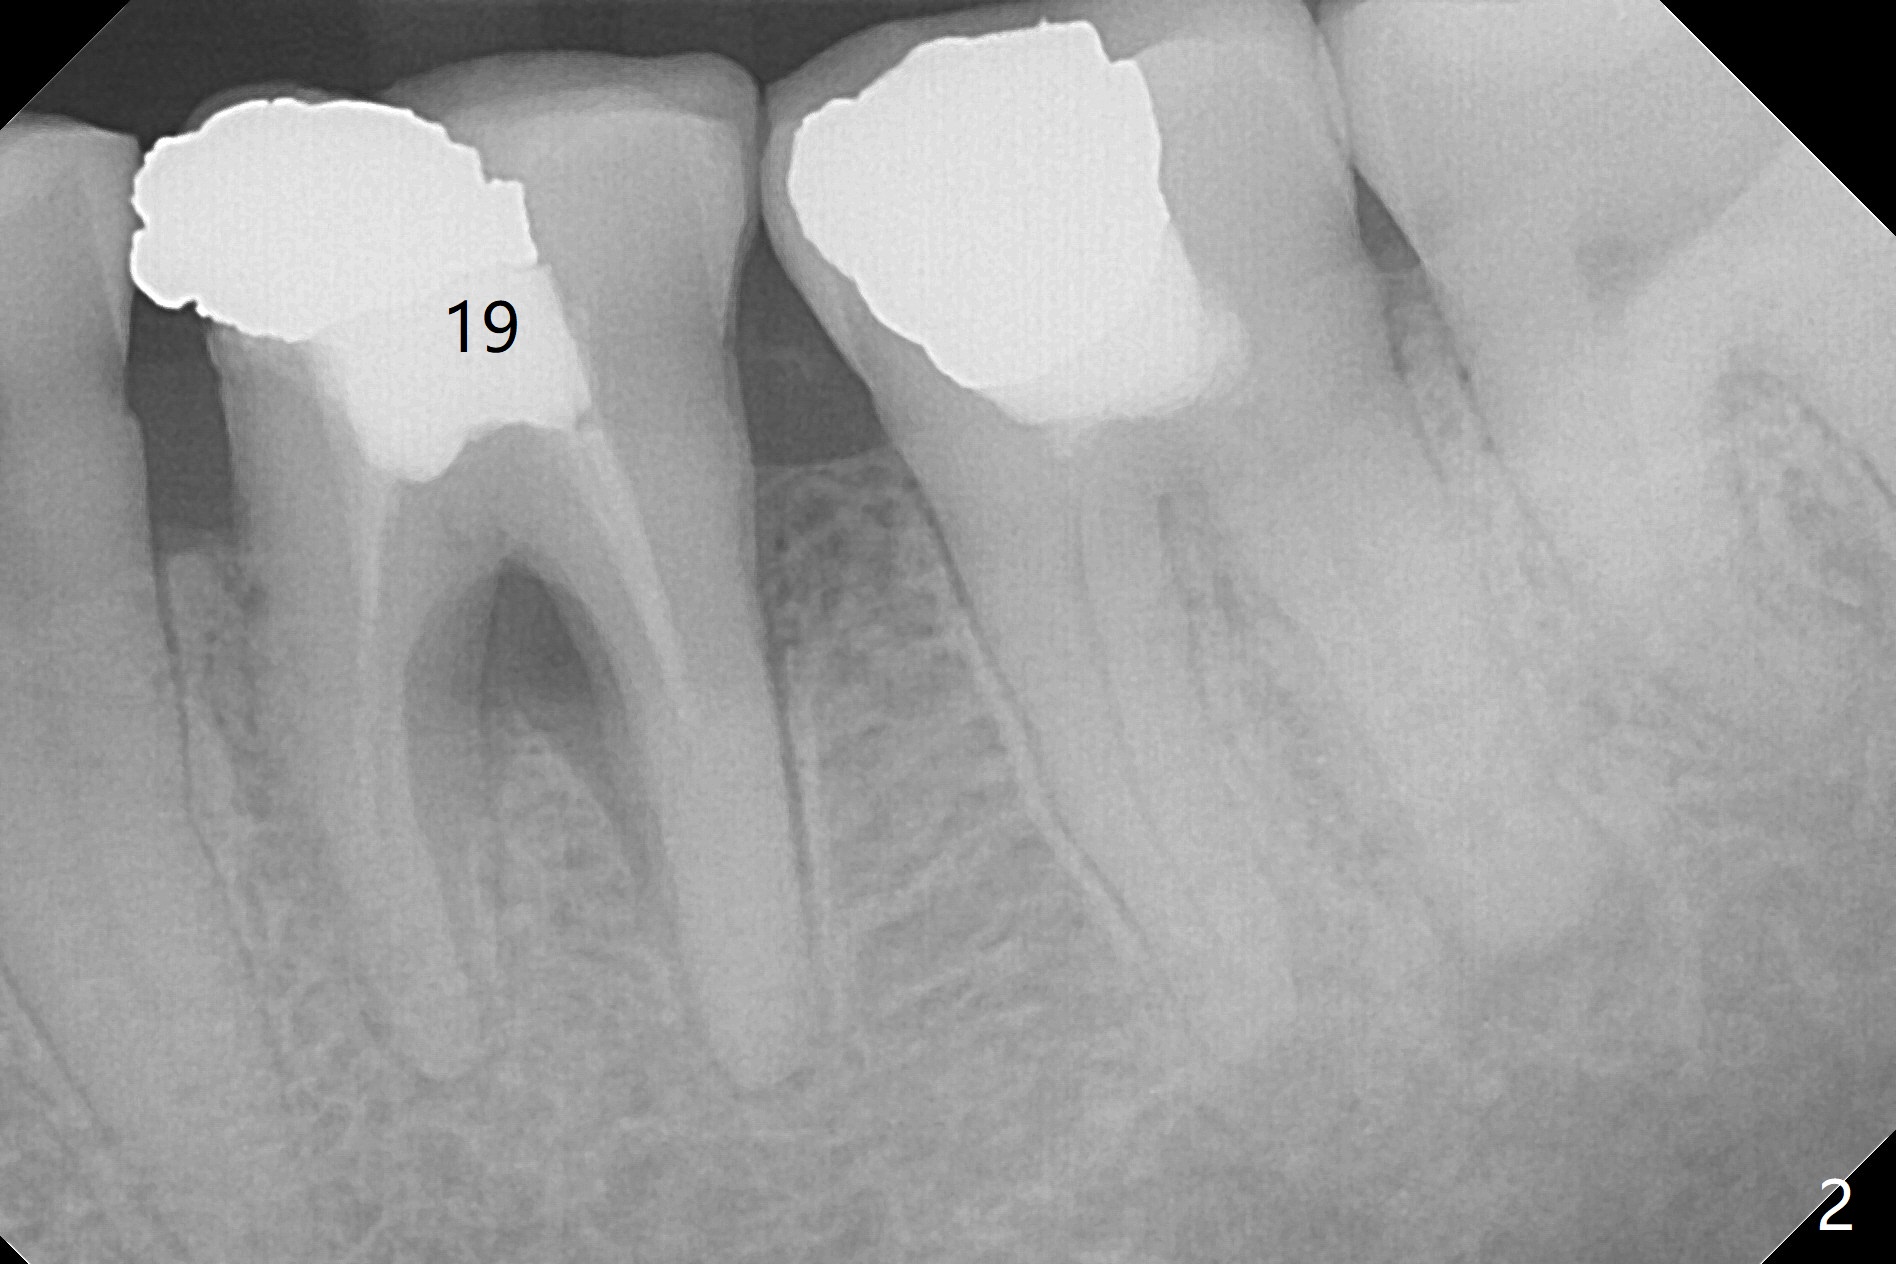

A 54-year-old man has several restoration with sign of bruxism (Fig.1). The tooth #19 has mesiodistal crack with furca radiolucency (Fig.2 *). To prevent abutment screw loosening associated with heavy mastication, a 6x17 mm tissue-level implant will be placed free hand due to the patient's tight schedule (blue, Fig.3,4,5). Pink: abutment; green: restoration which will be seated partially in the implant to reduce abutment loosening. To reduce possible neuropathy and have freedom to place implant deep, the implant length will be shorter, 14 mm, if the bone is dense. Take photos to show the crack line and buccal swelling. The patient returns for implant 4 months post extraction without bone graft in his home country with bone loss (Fig.6). In the presence of the accessory canal (Fig.7 *), a 5x10 mm implant is safe to be placed.